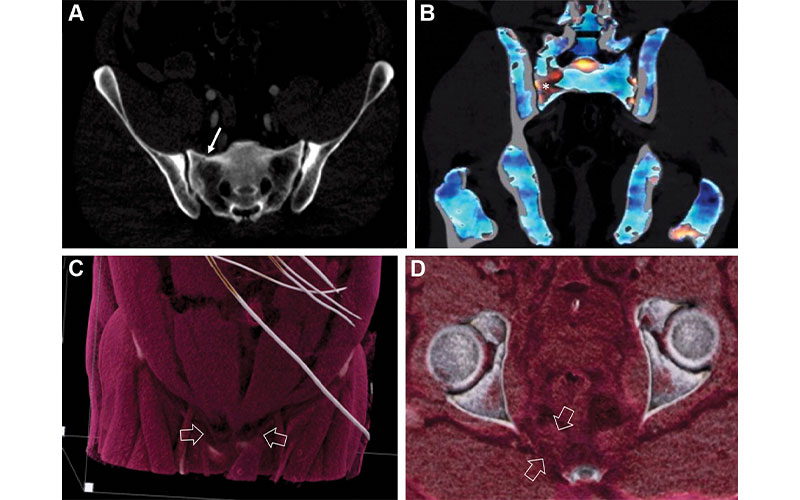

Images in a 42-year-old male pedestrian struck by a moving vehicle.

Yu et al, Radiology 2022; https://doi.org/10.1148/radiol.211679 ©RSNA 2022

Dual-energy CT provides information on traumatic bone bruising and marrow edema, and cinematic rendering generates lifelike images that give radiologists a direct view of injuries to surrounding ligaments and tendons. MRI is neither quick nor inexpensive, and often it’s not feasible to use in the acute period after major trauma.